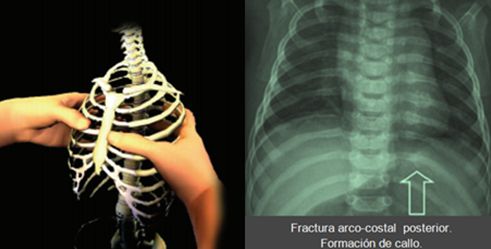

EL SINDROME DEL BEBE “SACUDIDO” (SHAKEN BABY SYNDROME)